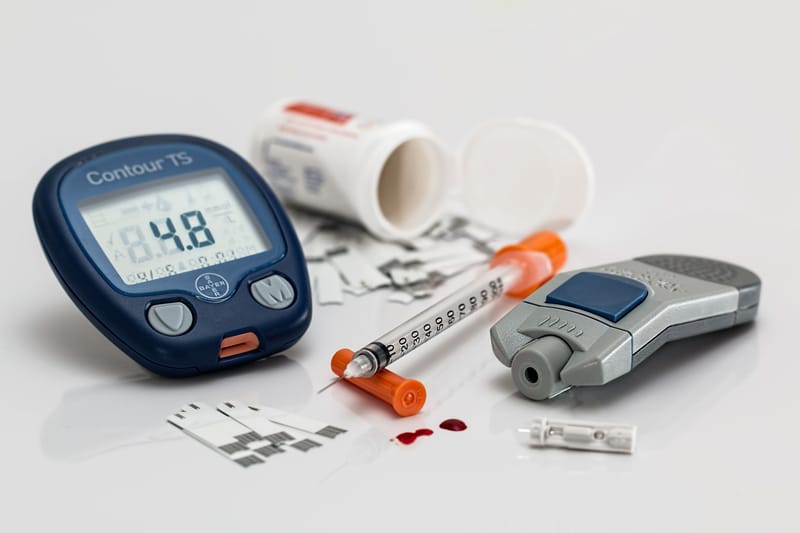

Oral and injectable systemic corticosterois are steroid hormones prescribed to decrease inflammation in diseases and conditions such as arthritis (rheumatoid arthritis, for example), ulcerative colitis, Crohn's disease, asthma, bronchitis, some skin rashes, and allergic or inflammatory conditions that involve the nose and eyes. Examples of systemic corticosteroids include hydrocortisone (Cortef), cortisone, prednisone (Prednisone Intensol), prednisolone (Orapred, Prelone), and methylprednisolone (Medrol, Depo-Medrol, Solu-Medrol). Some of the side effects of systemic corticosteroids are swelling of the legs, hypertension, headache, easy bruising, facial hair growth, diabetes, cataracts, and puffiness of the face